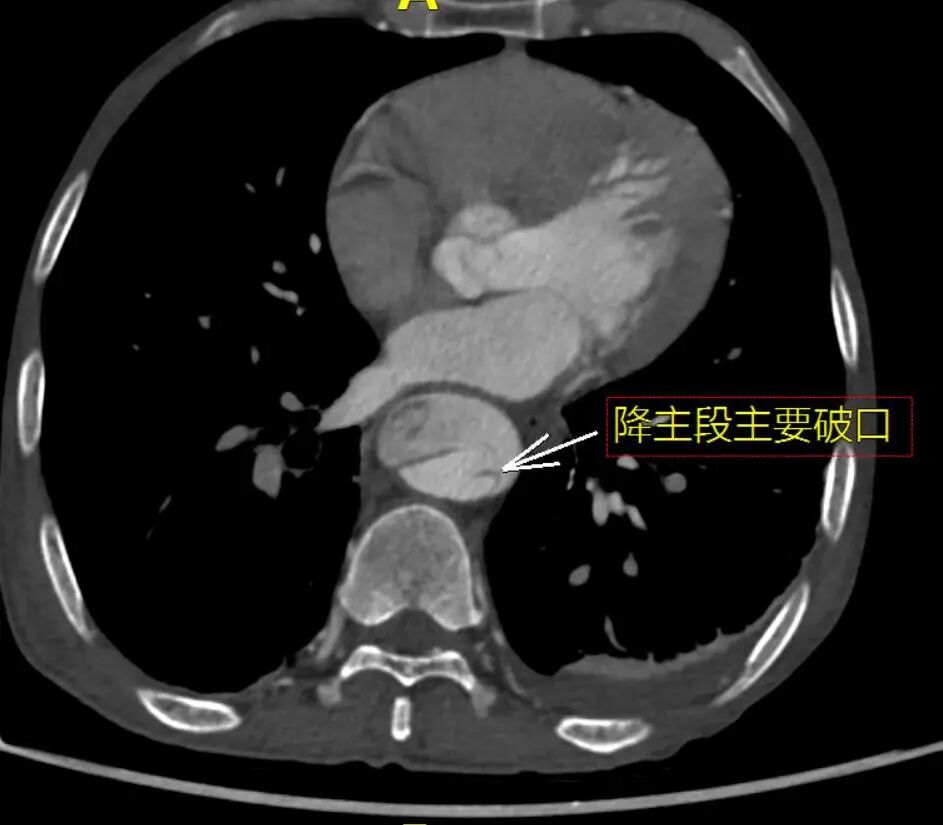

术前CTA详解

CTA提示患者主动脉弓型为Ⅲ型弓,左侧椎动脉为优势动脉,夹层累及至双侧髂外动脉,腹腔干动脉,肠系膜上动脉及左肾动脉为真腔供血,右肾动脉为真假腔供血,左侧胸腔少量积液。

降主段明显破口